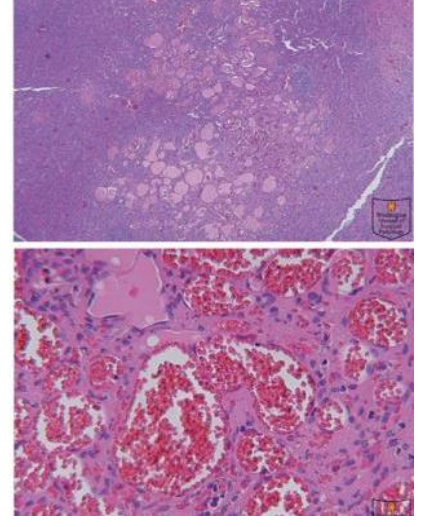

splenic infarct appearance

pale, tan, wedge shaped, esp if arterial

subcapsular

What is the MC primary tumor of the spleen?

hemangioma - usually cavernous type and less than 2 cm in size